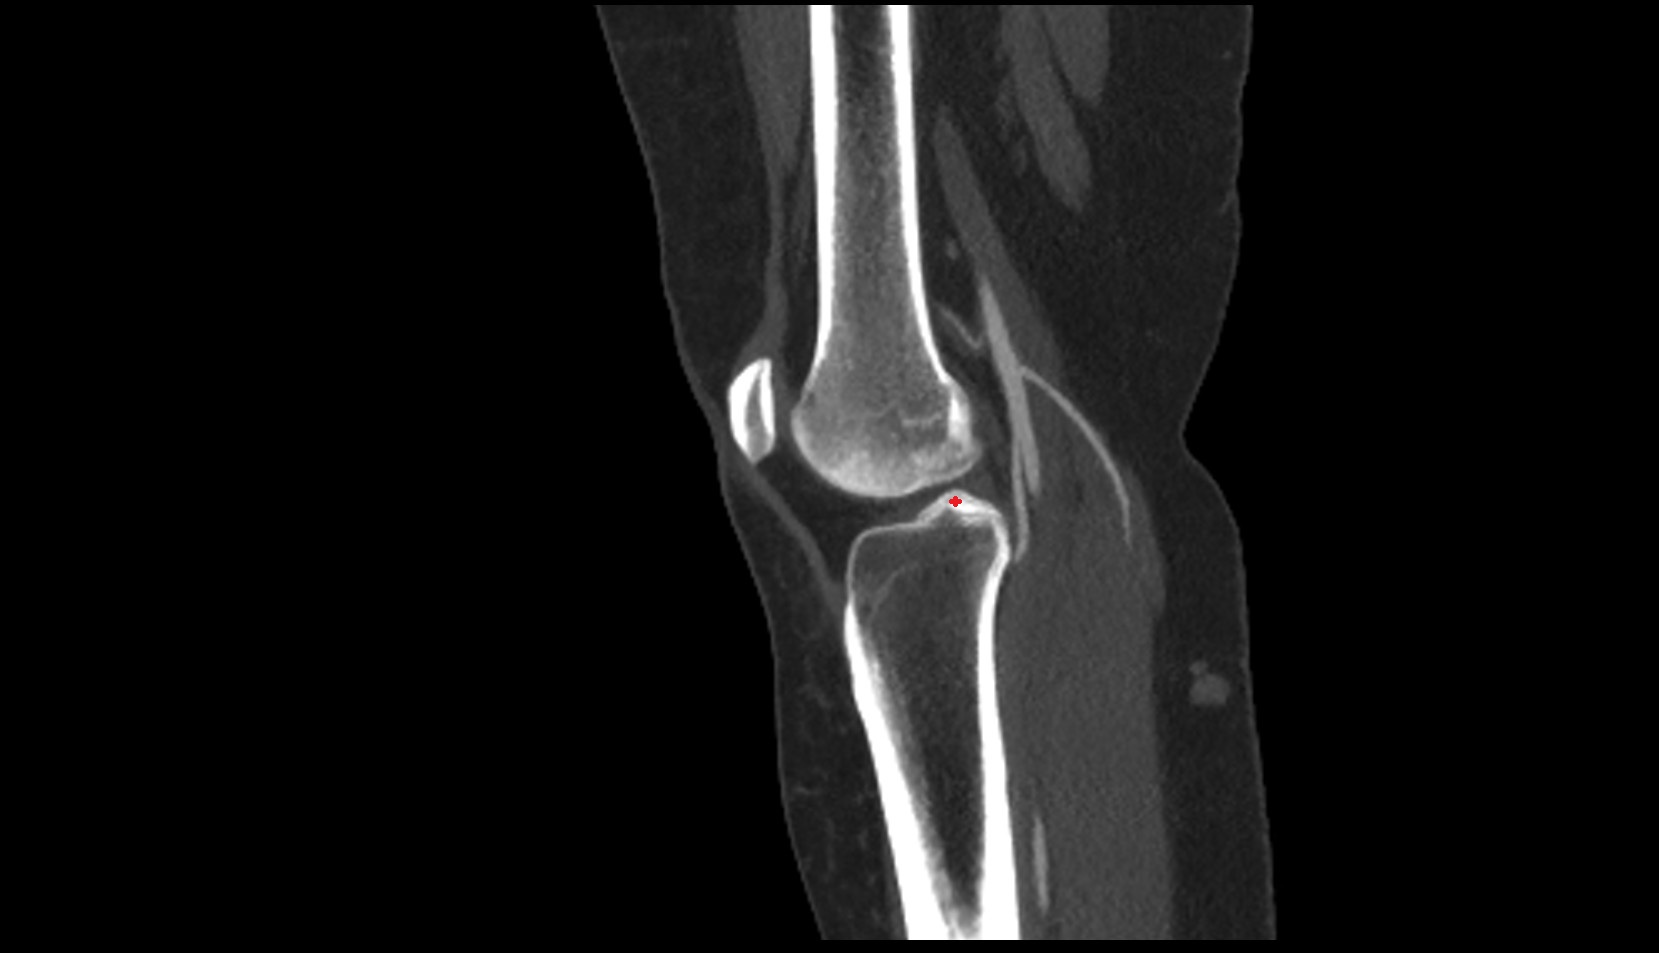

- Knee Joint